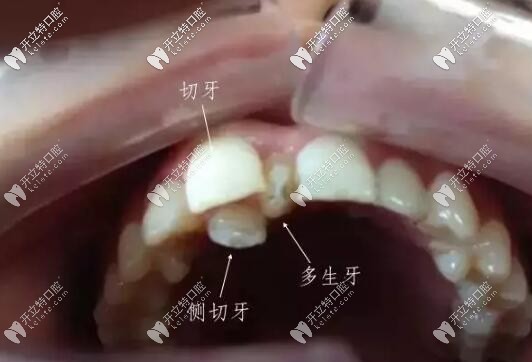

萌出的多生牙

智齒和多生牙并不是一個概念。多生牙從形態(tài)、牙根的數(shù)量,均不同于正常牙。